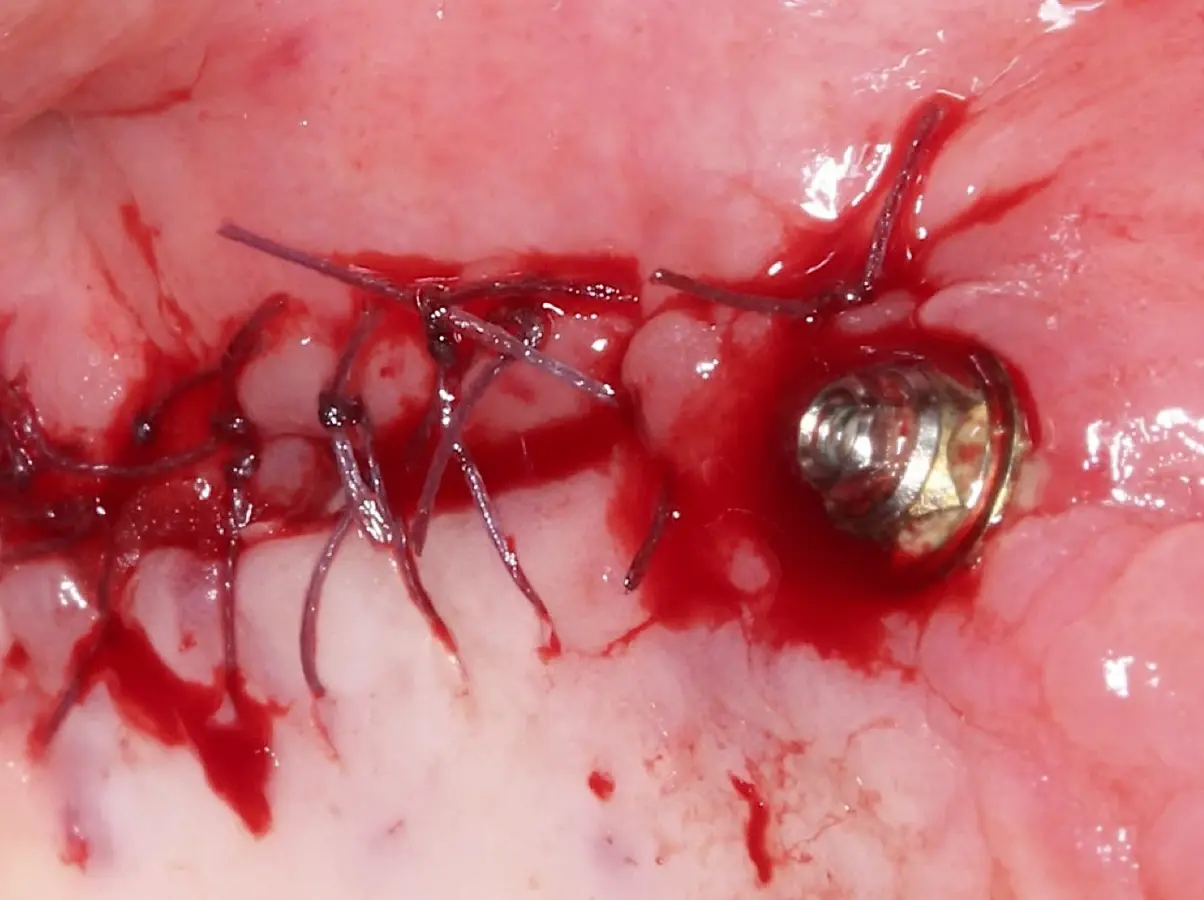

La técnica se inicia con la colocación de anestesia infiltrativa, posteriormente se realiza una incisión crestal o paracrestal con posibles liberantes verticales que deben de estar alejadas por lo menos 5 mm de los límites de la futura ventana y sobrepasar la línea mucogingival. Se realiza una elevación de colgajo, se inicia la antrostomía y antroplastía. Para ello, se emplea el inserto redondo diamantado de corte al momento de delimitar los bordes de la ventana de acceso. Luego se cambia al inserto aserrado liso de calibre fino con superficie diamantada, para profundizar y eliminar el hueso en el contorno de la ventana. Una vez que se traslucen los tejidos, se puede optar por el retiro de la tapa ósea o el levantamiento de ésta junto con la membrana.

Se inicia la elevación de la membrana de Schneider con el inserto redondeado no cortante en forma de disco, empleando movimientos suaves. El levantamiento puede complementarse con elevadores convencionales, siguiendo la dirección mesiodistal. La fase de desprendimiento inicia con el piso y sigue hacia la pared mesial para terminar, y de ser necesario, hacia la pared posterior. Existen diversos insertos con angulaciones y longitudes para mayor accesibilidad16 (Figura 1).